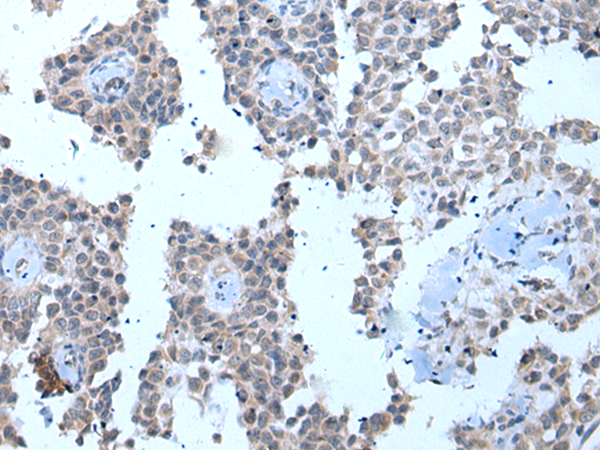

IHC positive control: |

Human ovarian cancer |